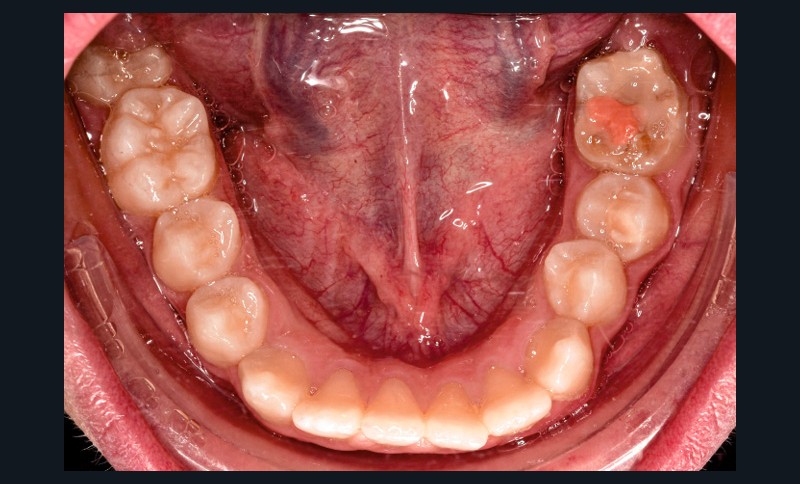

L’examen clinique montre une MIH sévère sur 16, 26, 36 et 46, et modérée sur 11 et 21.

Sur le plan alvéolo-dentaire (fig. 1b) :

- Classe II subdivision gauche avec déviation du point inter-incisif mandibulaire à gauche ;

- occlusion inversée entre 22 et 32 ;

- dysharmonie dento-arcade (DDA) sévère ;

- 13 en position haute retenue.